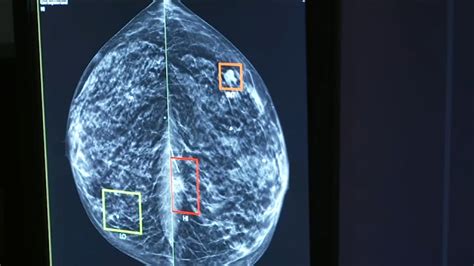

To understand why advanced imaging is necessary, it helps to know what “density” actually refers to. Breast tissue is composed of two primary types: fibrous and glandular tissue (which are dense) and fatty tissue (which is non-dense). When a radiologist looks at a mammogram, fatty tissue appears dark or transparent, while dense tissue appears solid white.

The challenge arises because breast cancer also appears as a white area on a standard mammogram. If a woman has dense breasts, the white dense tissue can essentially “mask” or hide a potential tumor, making it significantly harder to detect abnormalities. This is where the shift toward more sophisticated technology is vital.

For decades, standard 2D digital mammography was the gold standard. However, 2D images take a flattened view of the entire breast, which can lead to overlapping tissues that look like suspicious spots. A Dense Breasts 3D Mammogram, clinically known as digital breast tomosynthesis, works differently by taking multiple images from various angles. These images are then reconstructed into a series of thin “slices,” allowing the radiologist to scroll through the breast tissue layer by layer.

The interpretation of a Dense Breasts 3D Mammogram requires specialized training. Radiologists must analyze hundreds of individual slices to ensure no subtle changes are missed. By utilizing the 3D data, they can isolate specific areas of concern that might have been buried under dense, fibroglandular tissue in a 2D scan. This technological precision empowers medical professionals to provide more confident assessments, ultimately leading to better peace of mind for the patient.